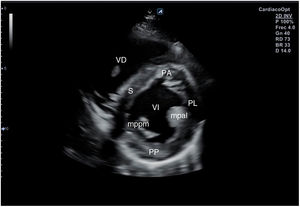

Desde el plano anterior, sin cambiar el apoyo de la sonda, se realiza un giro de 90° en sentido horario, obteniendo el plano paraesternal de eje corto, que es un corte perpendicular al anterior (fig. 4). En este eje, basculando la sonda, se puede cortar de forma transversal el corazón desde el ápex, si se angula hacia la cadera izquierda, pasando por los músculos papilares (fig. 5) hasta la base, donde están la válvula mitral (fig. 6) y aórtica (fig. 7), si se hace hacia el hombro derecho.

En este plano se visualizan todas las paredes del VI. A nivel de la válvula mitral se observa el orificio valvular, sus valvas con las comisuras, el tabique interventricular y las paredes libres de ambos ventrículos.